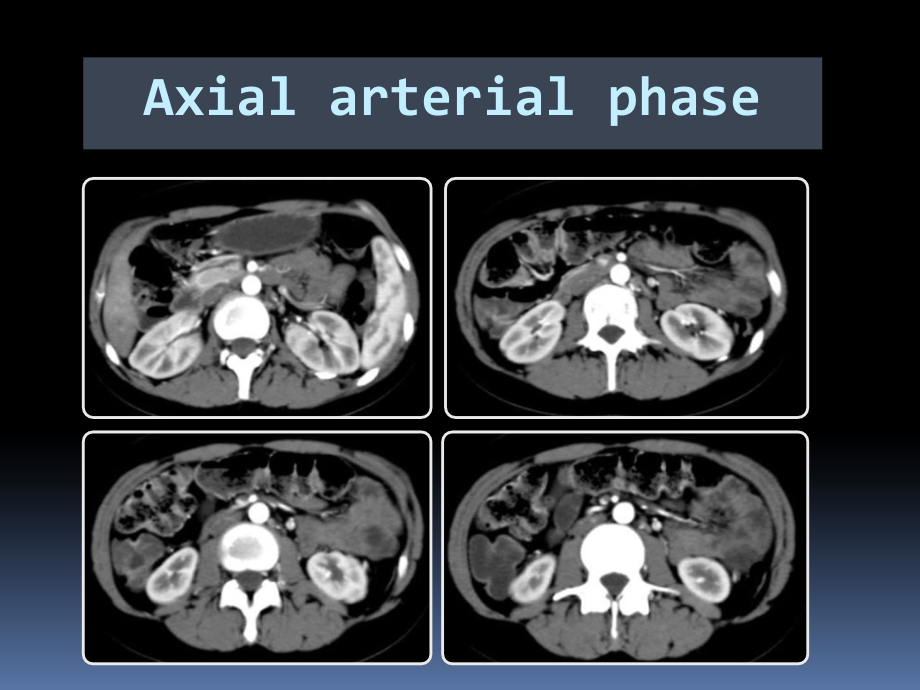

,单击此处编辑母版标题样式,单击此处编辑母版文本样式,第二级,第三级,第四级,第五级,2016/5/24,#,Case Discussion,Tang Chun Xiang,2016/5/25,Axial arterial phase,Axial arterial phase,Axial venous phase,Coronal arterial phase,Sagittal venous phase,Crohn disease,An inflammatory disease of the gastrointestinal tract that typically has an indolent course,Characterized by intestinal,ulceration,strictures,and,fistula formation,Commonly affects,young adults,small bowel,particularly the,terminal ileum,Small bowel involvement in Crohn disease is typically,transmural,with,skip lesions,CT,and,MRI,Introduction-,Crohn disease,CT and MRI,Useful for differentiating between,active,and fibrotic bowel strictures,Allowing visualization of the entire,thickness,of the bowel wall,Depicting,extraenteric involvement,Providing more detailed and comprehensive information about the,extent and severity,Introduction-,Crohn disease,Comb sign,Fat halo sign,Bowel wall enhancement,Bowel wall thickness,Stricture and fistula,Mesenteric/intra-abdominal abscess(15%-20%)or phlegmon formation,Ulcerations and loss of haustration,Creeping fat,Imaging findings on CT and MRI,Comb sign,Prominence of the vasa recta adjacent to the inflamed loop of bowel,Transmural extension of inflammation across the serosa and to engorgement of the hyperemic vasa recta surrounding the inflamed bowel segment,Not pathognomic of Crohn disease,Imaging findings on CT and MRI,Fat halo sign,Infiltration of the submucosa with fat,between the muscularis and the mucosa,Confused with the fat ring sign of mesenteric panniculitis,Nearly pathognomonic of inflammatory bowel disease(Crohn disease and ulcerative colitis),Imaging findings on CT and MRI,Bowel wall enhancement,The result of increased vascular permeability and angiogenesis,The,most sensitive indicator,of active Crohn disease,Enhancement can be graded by comparing to the precontrast images,Minor,increased enhancement,Moderate,enhancement,Marked,enhancement,No abnormal enhancement:equivalent to normal bowel wall,Imaging findings on CT and MRI,Homogeneous,Mucosal,Layered,Pattern of enhancement,Bowel wall thickness,Normal bowel wall thickness,:,lumen distended,,,1-2 mm,;,lumen collapsed,3-4 mm,Mild,:3-5 mm,Moderate,:5-7 mm,Marked,:7mm,One of the most common signs,but not specific,Correlates well with the severity of the disease activity,Measure when lumen distended well,Black border artifacts can distort thickness measurements,Imaging findings on CT and MRI,Stricture,A complication of Crohn disease,Reversible strictures produced by active disease,A lack of enhancement and loss of stratification might be seen in the presence of transmural fibrosis,Imaging findings on CT and MRI,Fistula,The detection of penetrating disease is important and may redirect or alter management,Enteroenteric fistula,enterovesical fistula,and interloop abscess,CT enterography resulted in accurate detection of fistulas in,94%,of cases,Imaging findings on CT and MRI,Abscess,Often seen in patients with severe active Crohn disease,Extraluminal fluid collections without communication with the bowel lumen,Fluid collections with an enhancing wall with or without associated air,Imaging findings on CT and MRI,Ulceration,Moderate to deep ulceration can be seen,small ulcerations can be difficult to distinguish,Active spots of inflammation,Increased enhancement,Imaging findings on CT and MRI,Loss of haustration,Both the colon and the small bowel are involved in 30%60%,Involvement of the colon alone in 20%35%,A decrease of haustral folds,A common finding in ulcerative colitis,Imaging findings on CT and MRI,Creeping fat,Fibrofatty proliferation of fat wrapping,different name for hypertrophy of the subserosal fat,Common finding in longstanding Crohn disease,The image shows creeping fat surrounding bowel loops,Imaging findings on CT and MRI,CT and MRI,Useful for differentiating between active and fibrotic bowel strictures,Summary,CT features of active Crohn disease,Mucosal hyperenhancement,Wall thickening(thickness 3 mm),Mural stratification with a prominent vasa recta(comb sign),CT features of inactive longstanding Crohn disease,Submucosal fat deposition(fat halo sign),Surrounding fibrofatty proliferation(creeping fat),and fibrotic strictures,Pseudosacculation,CT and MRI,Allowing visualization of the entire thickness of the bowel wall,Summary,Normal bowel wall thickness,:,lumen distended,,,1-2 mm,;,lumen collapsed,3-4 mm,Mild,:3-5 mm,Moderate,:5-7 mm,Marked,:7mm,CT and MRI,Depicting extraenteric involvement,Summary,Fistula and abscess,Enteroenteric fistula,Enterovesical fistula,Interloop abscess,Etc.,CT and MRI,Providing more detailed and comprehensive information about the extent and severity,Summary,The extent and severity correlates with the disease,The degree of thickening,The intensity of enhancement,Fistulas and abscess,The presence of ulcerations and loss of haustration,THANK YOU!,